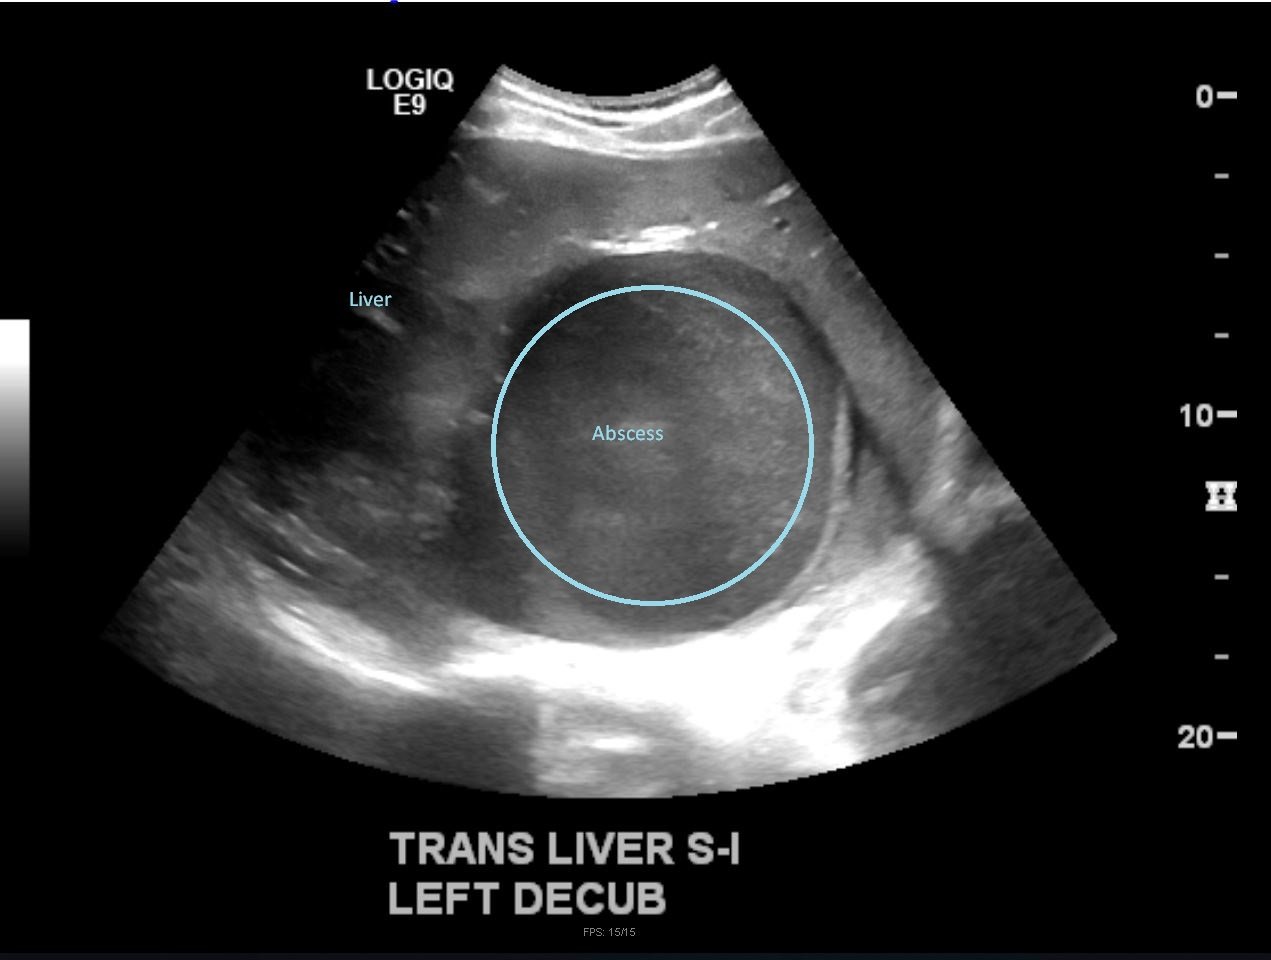

Although rare in the developed world, amebic infections are common worldwide and represent a challenging and often overlooked diagnosis. In this case, an amebic liver abscess was discovered in a 29-year-old male who presented to the emergency department (ED) complaining of right upper quadrant abdominal pain, weight loss, non-bilious/non-bloody vomiting, and diarrhea for three months. He recently traveled to India and Mexico. Point-of-care ultrasound discovered a liver mass and computed tomography (CT) confirmed the presence of a liver abscess. The case highlights the usefulness of ultrasound as an initial diagnostic tool, the importance of careful travel history in patients with suspected infectious diseases, and the initial provision of broad-spectrum coverage for bacterial and amebic pathogens for liver abscesses until the pathogen has been identified.